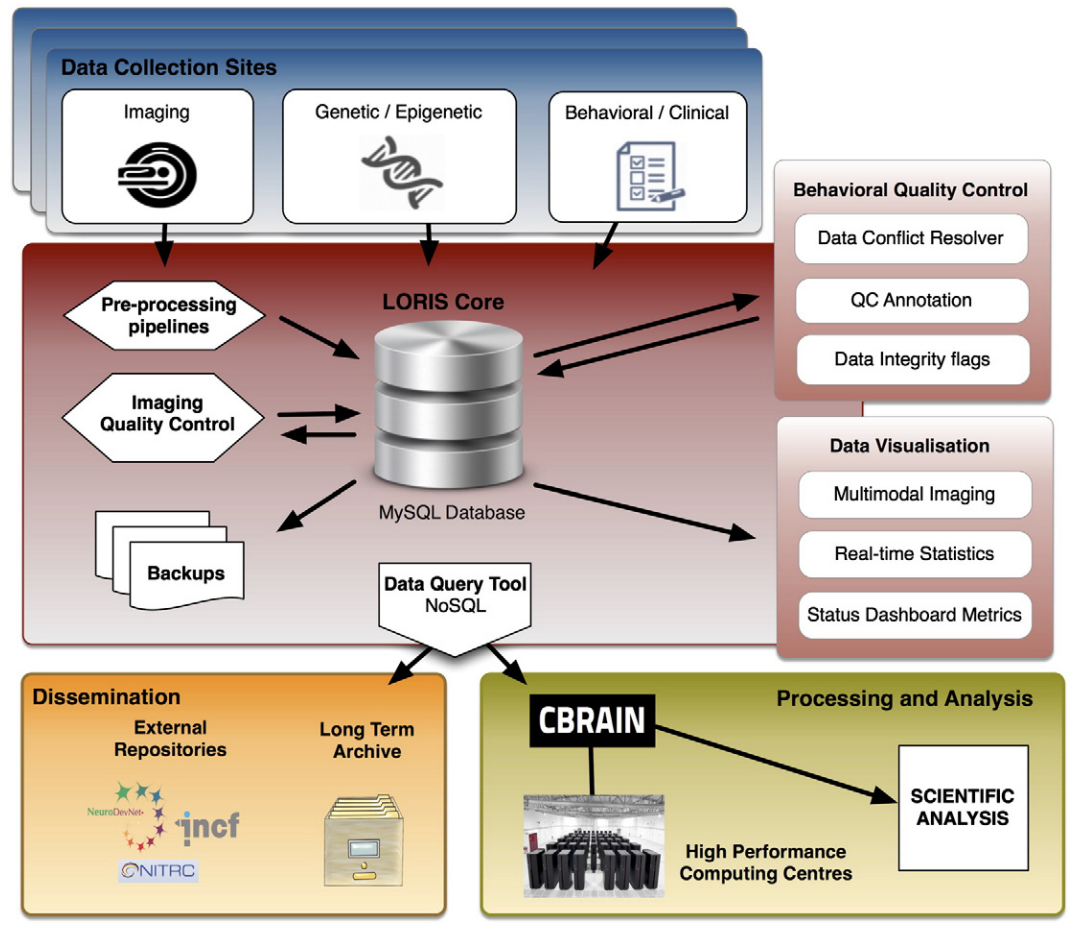

“..is a modular and extensible web-based data and project management software for neuroimaging research studies. It is an OPEN SOURCE framework and database suitable for managing large datasets.” |

Heterogenous data acquisition |

Storage, processing & dissemination |

What does LORIS do?

What does LORIS do?

Extensible and modular design

Heterogenous Data

Imaging Data

1. Acquisition & Storage

2. Visualisation:

Imaging Browser, BrainBrowser3. Quality Control:

Radiological Review Module, DCC MRIData Querying

- Imaging Statistiscs

- Data Querying Tool (DQT)

What can LORIS do (pointform)

- Long Term Storage - Large datasets are valuable assets (e.g. ADNI)

- Anonymity/Privacy - Ethics/IRB compliance and patient confidentiality

- Data Sharing - Cross project collaborations

- Secure Web Access- Available through a web browser

- Heterogeneous Data Management - Single platform for MRI, PET, Clinical & Genetics data

- Multimodal Data Querying - Easy querying of data, without requiring a programmer

- Quality Control - Protocol violations, artefact detector, inter-rater reliability

- Summary Statistics - Demographics, imaging, data entry

- Processing Platform - Seamless serving of data to processing environments

- Radiological Reviews - Visualization, including module to curate

- Import/Export Capabilities - .xls, .csv, etc.

- Biobanking - Tissue, blood and saliva samples

- Visualization - 3D and 4D

- Customizable & Extensible - New modules and features are possible

- Open Source - Full access to source code. Code is free.